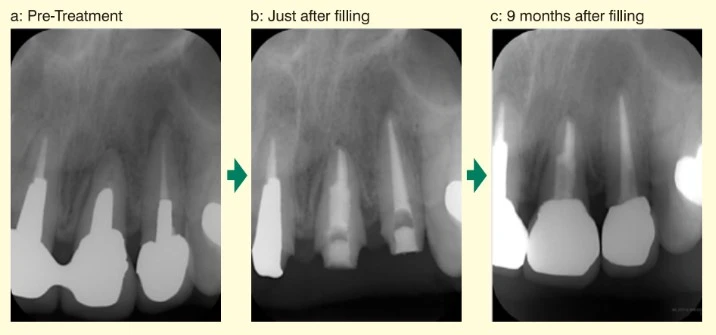

Các tổn thương quanh chóp được tìm thấy trong một bức ảnh X-quang trước khi điều trị.

Sau khi điều trị, cả 2 ống tủy được trám bít bằng BG Multi với kỹ thuật hình nón đơn.

Hình chụp Xquang cho thấy các tổn thương quanh chóp giảm dần sau 9 tháng. Điều này hỗ trợ các kết quả thử nghiệm của chúng tôi, cho thấy rằng BG Multi không đè nén hay tạo áp lực trong quá trình chữa lành vết thương của mô quanh chóp.